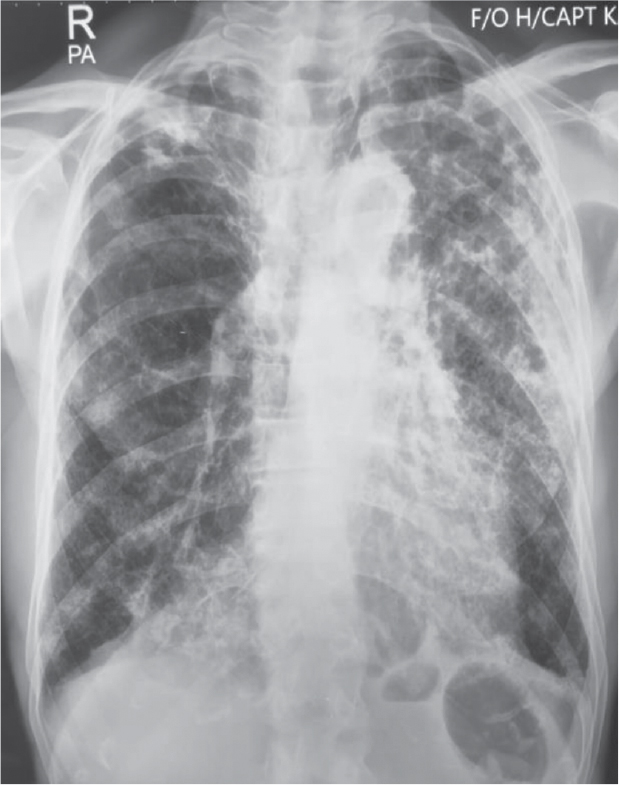

Chest radiography demonstrated a hyperinflated lung field with reticular opacities in the right upper zone, left upper and middle zones with nonhomogenous air space opacities and features of volume loss in the form of rib crowding in the left upper and middle zone (Fig. 1).

Figure 1. Chest radiography (PA view) demonstrating a hyperinflated lung field with reticular opacities in the right upper zone, left upper and middle zone. Left upper and middle zone shows rib crowding along with nonhomogenous air space opacities.